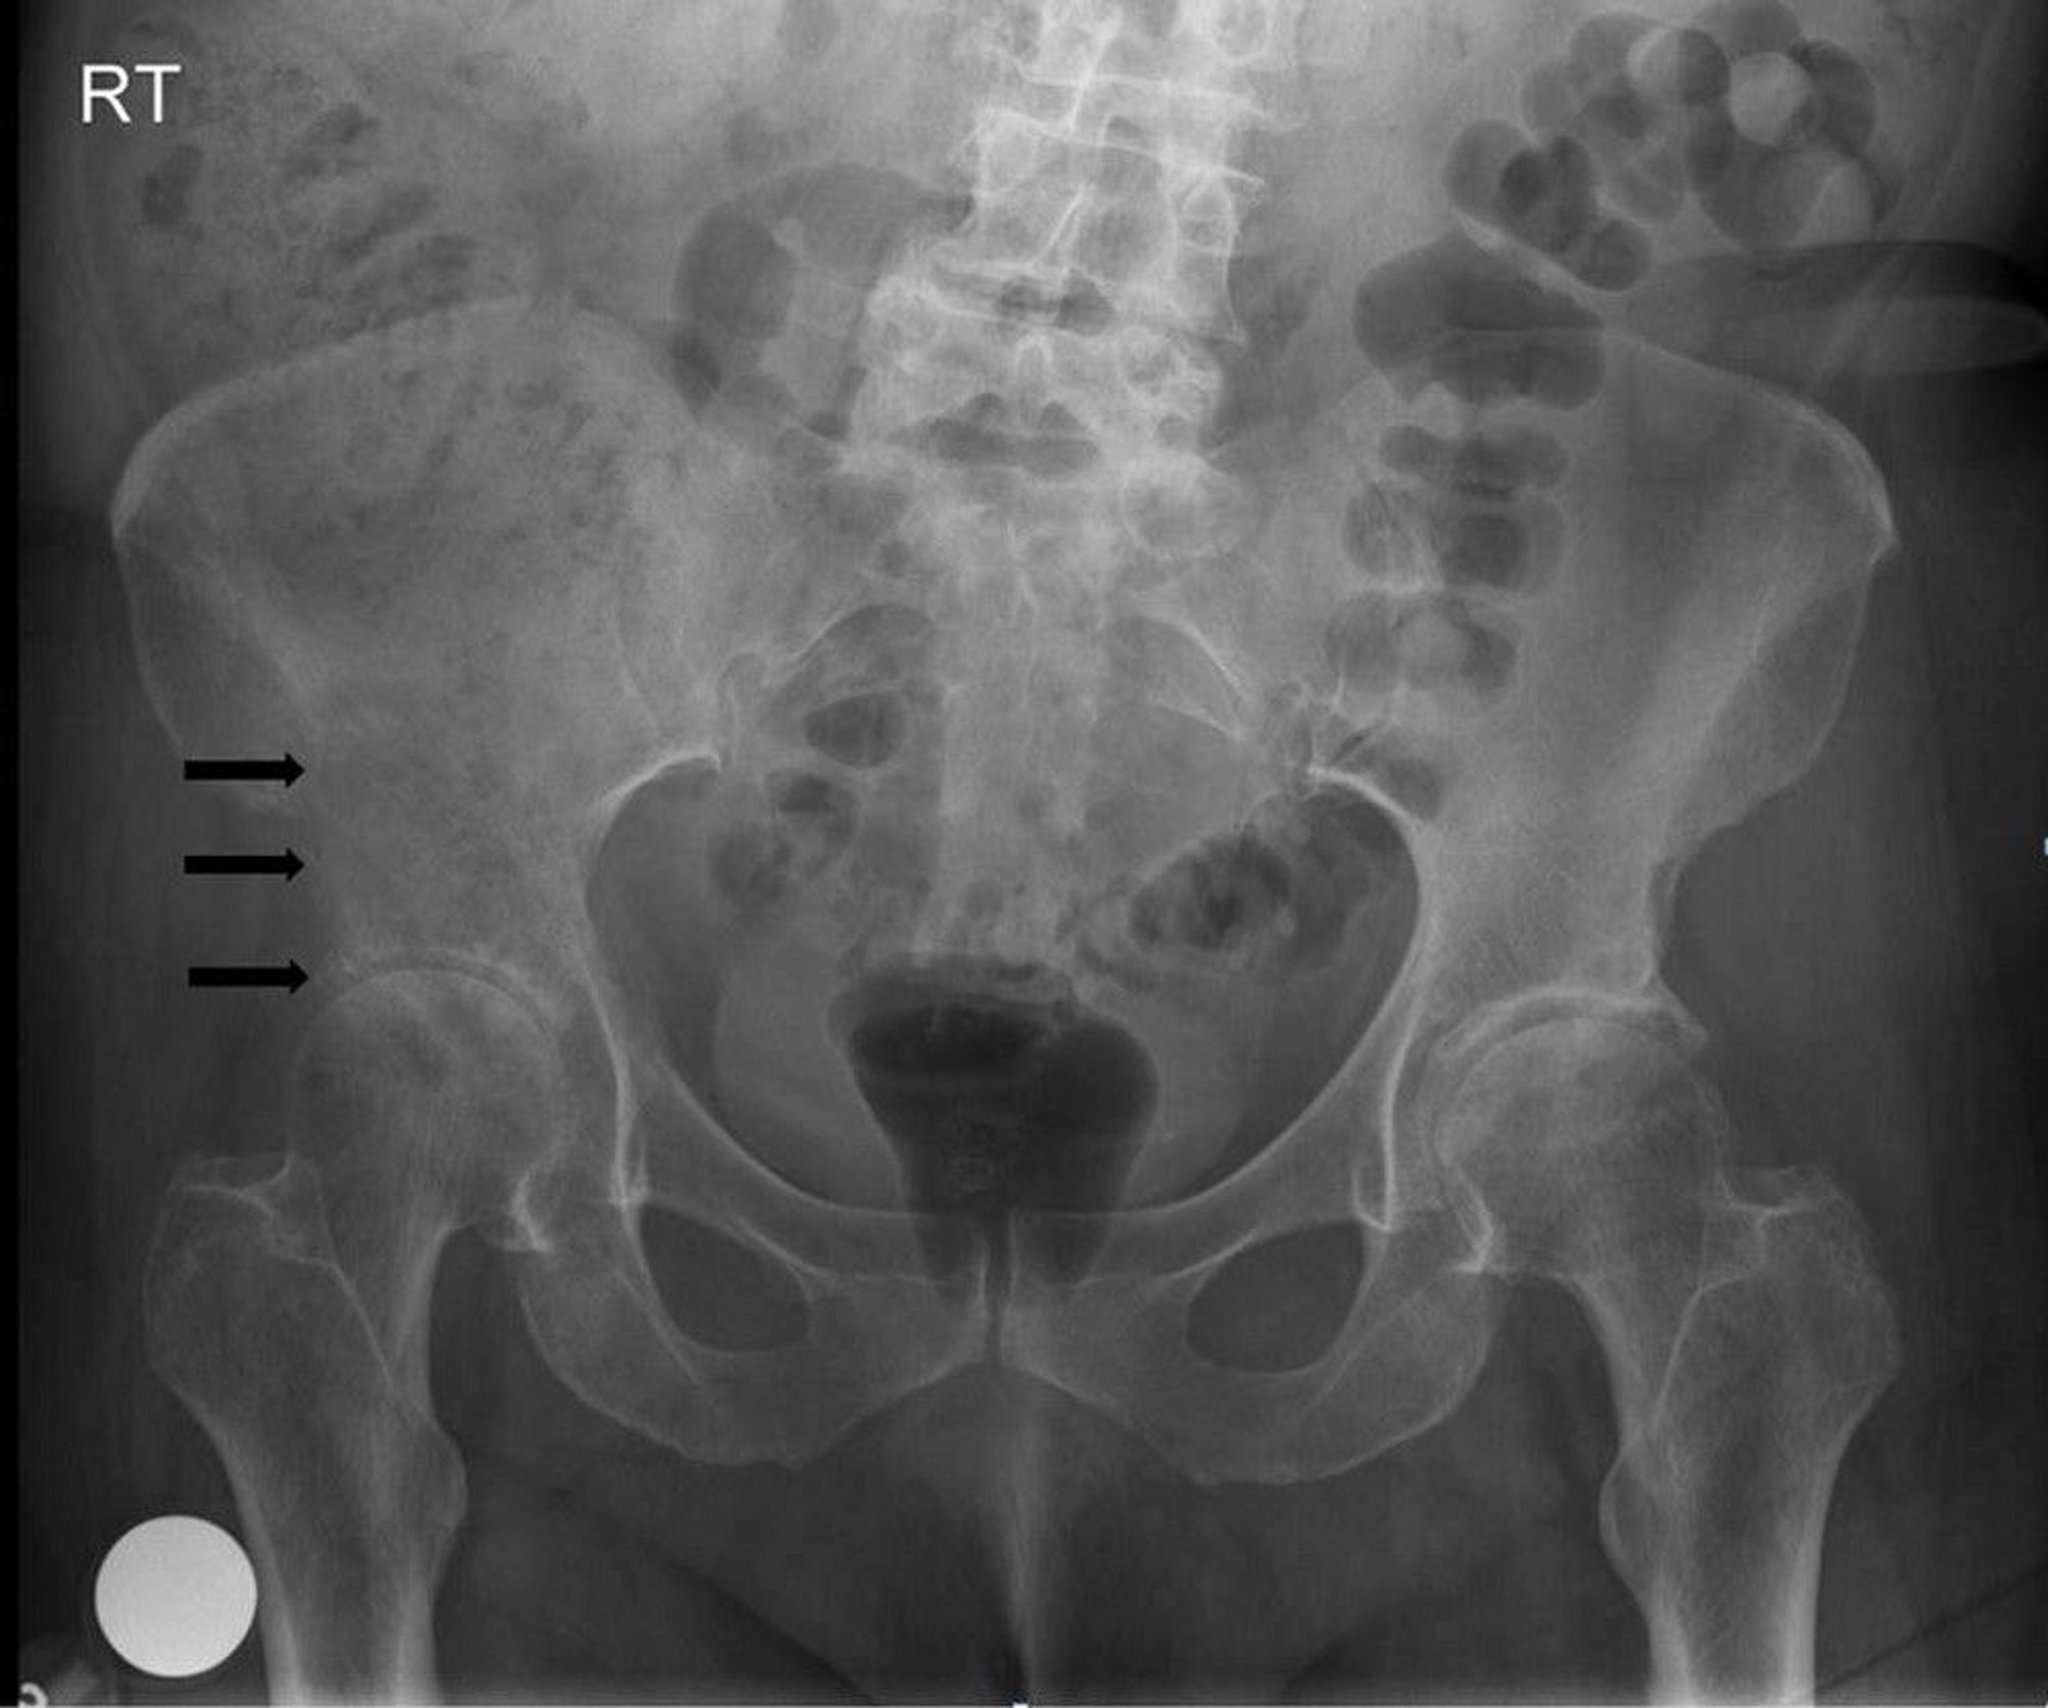

This radiograph of the pelvis shows a lytic, destructive lesion at and above the right acetabulum (arrows), consistent with a metastasis.

Image courtesy of Michael J. Joyce, MD, and Hakan Ilaslan, MD.